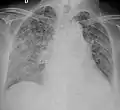

A case of miliary tuberculosis in an 82-year-old woman:

X-ray, 13 days after onset, showing bilateral interstitial infiltrates